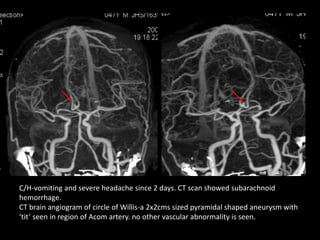

C/H-vomiting and severe headache since 2 days. CT scan showed subarachnoid

CT brain angiogram of circle of Willis-a 2x2cms sized pyramidal shaped aneurysm with